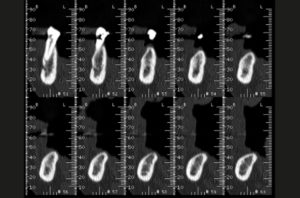

L’esame Cone Beam ci permette di evidenziare le strutture anatomiche di interesse, i forami mentonieri e il canale incisivo; grazie allo studio dell’esame 3D, vista la disponibilità ossea e la presenza di un osso denso (Figg. 3-6), si decide di utilizzare due impianti Leone diametro 3,3 mm e lunghezza 12 mm e due impianti Leone diametro 3,3 mm e lunghezza 10 mm.

- Fig. 3

- Fig. 4

- Fig. 5

- Fig. 6